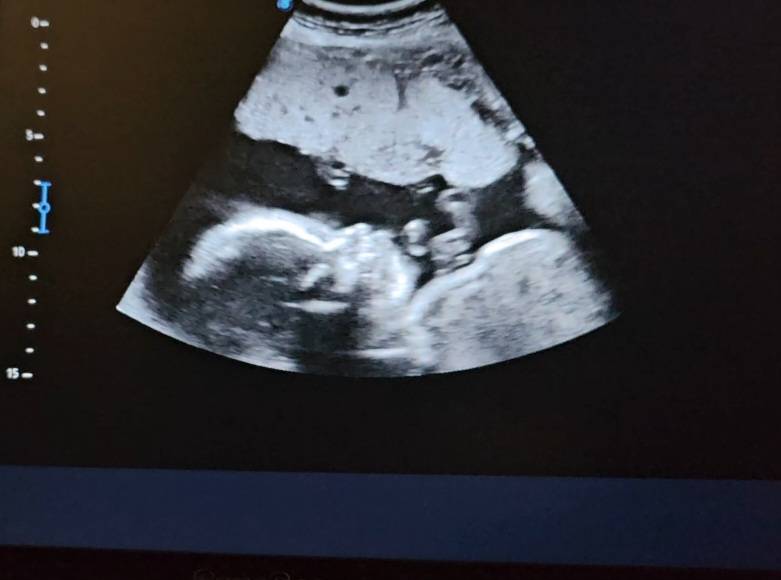

Сходила сегодня на встречу к малышу🥰 1,5 месяца не виделись🥹

В 19 недель был 300гр, сейчас уже 1кг

Растём☺️ также опережает на неделю.

Маленький курносый носик🥹 весь в мать😄